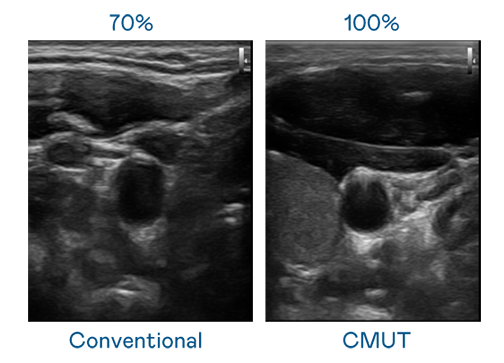

CMUT 技术是一种用电容式微机电元件来产生超音波讯号的技术。与传统 PZT 压电式技术相比,CMUT 频宽增加 30%,更宽频的超音波讯号让影像解析度大幅提升,是实现高影像品质医疗超音波扫描、促进精准医疗发展的关键技术。

大频宽带来超清晰影像

超音波影像的解析度高低,首先取决于探头能发出的讯号频宽。人生就是博·z6尊龙 CMUT 可提供高清晰的超音波讯号,提供高频宽、高灵敏度、影像纹理细节更高的超音波影像,协助医护人员缩短影像判读时间及利用精准的医疗影像进行诊断。